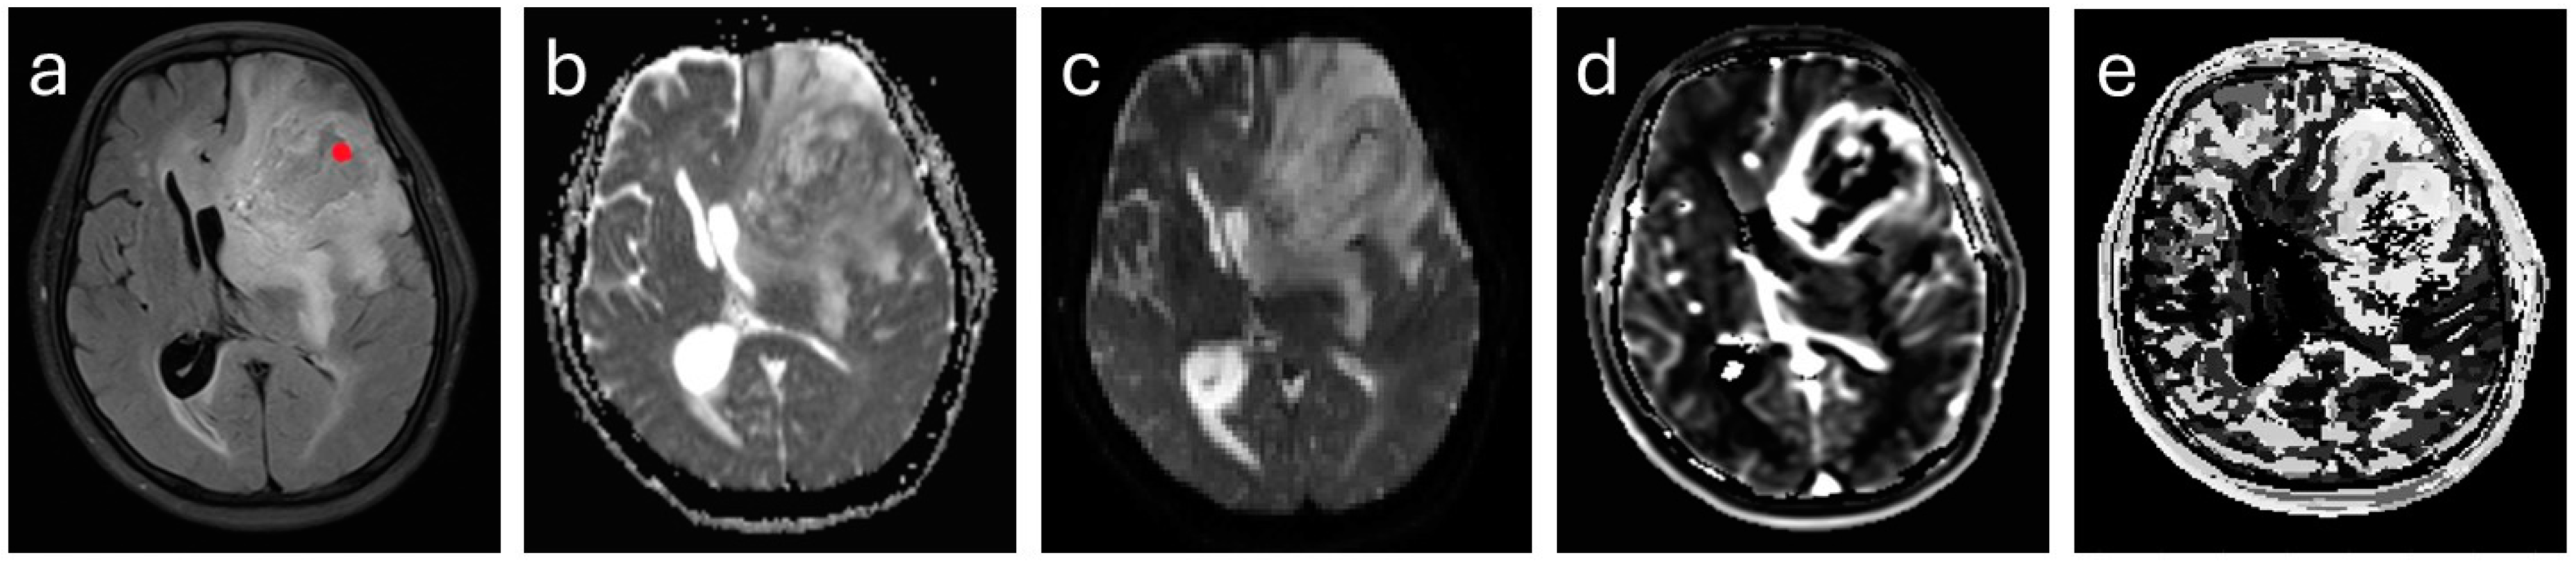

2.3. MR Imaging

2.4. Image Analysis

3.2. Evaluation of the Individual and Combined DCE-MRI and DKI Parameters